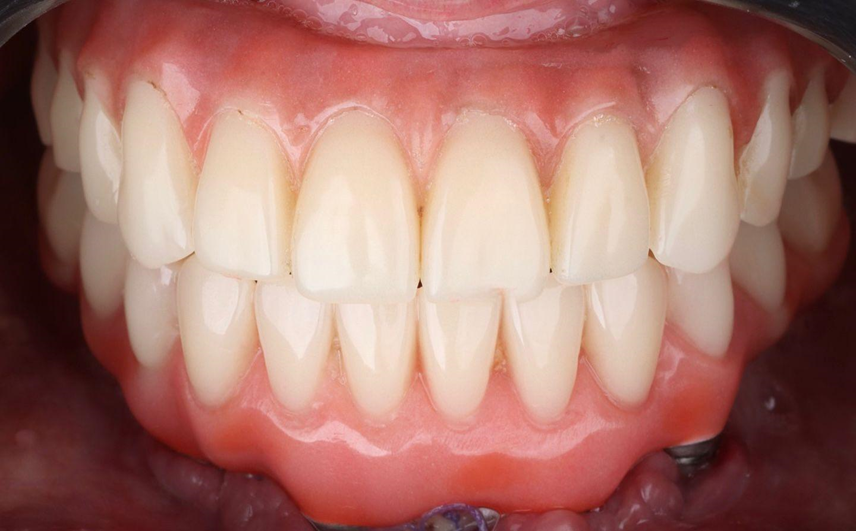

Paciente de 62 anos, do sexo feminino, sem comorbidades e história médica pregressa, apresentava severa reabsorção óssea em regiões anteriores e posteriores da mandíbula devido a uma peri-implantite (Figuras 1A e 1B). Feita a remoção dos implantes, a paciente optou por utilizar uma prótese total mucossuportada até a nova intervenção com prótese do tipo protocolo inferior. Após seis meses, a mandíbula encontrava-se cicatrizada (Figura 2). Como parte do protocolo diagnóstico, foi realizada tomografia computadorizada pela técnica do duplo DICOM. Com a severa perda óssea em região anterior de mandíbula, optamos por realizar a cirurgia de forma guiada, aumentando a previsibilidade e precisão da cirurgia. Os arquivos obtidos foram exportados para o software CoDiagnostiX, possibilitando a realização do planejamento reverso e o subsequente posicionamento virtual dos implantes (Figura 3). Com base no planejamento, optou-se pela instalação de quatro implantes Implacil Osstem CM AR Due Cone (3,5 x 7 mm), associados a mini-cônicos de 1,5 mm (Figuras 4A, 4B, 4C, 4D e 4E). A partir da tomografia da prótese da própria paciente, confeccionaram-se duas guias cirúrgicas: uma guia de pino de fixação (Figura 5) e uma guia de fresagem para a instalação dos implantes (Figura 6). Durante o procedimento cirúrgico, inicialmente foi posicionada a guia de pino de fixação para fresagem dos pinos de fixação e orientação da sequência cirúrgica (Figura 7). Após essa etapa, a guia foi substituída pela guia de fresagem dos implantes (Figura 8), utilizada para a fresagem e inserção dos implantes planejados (Figura 9). Concluída a instalação, optou-se por seguir o fluxo analógico, com a adaptação dos mini-cônicos 1.5 mm (Figura 10), realização da transferência de moldagem com silicona de adição leve e sutura com fio absorvível Vycril 6-0. O guia inicial foi adaptado com broca Maxicut, possibilitando sua utilização como molde de orientação para o laboratório protético (Figura 11). Após a moldagem, foram posicionadas as tampas de proteção sobre os implantes. Na fase protética, transcorridas 48 horas do procedimento cirúrgico, foi realizada a prova clínica da barra metálica e dos dentes (Figura 12). Na etapa subsequente, 72 horas após a cirurgia, procedeu-se à instalação e entrega do protocolo mandibular inferior e radiografia prévia, reabilitando funcional e esteticamente a paciente em curto espaço de tempo (Figuras 13A e 13B).